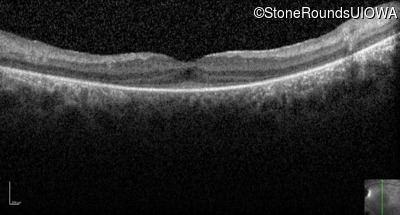

Age at visit: 15 years

This 15 year old male has had very poor vision and nystagmus since the first year of life.